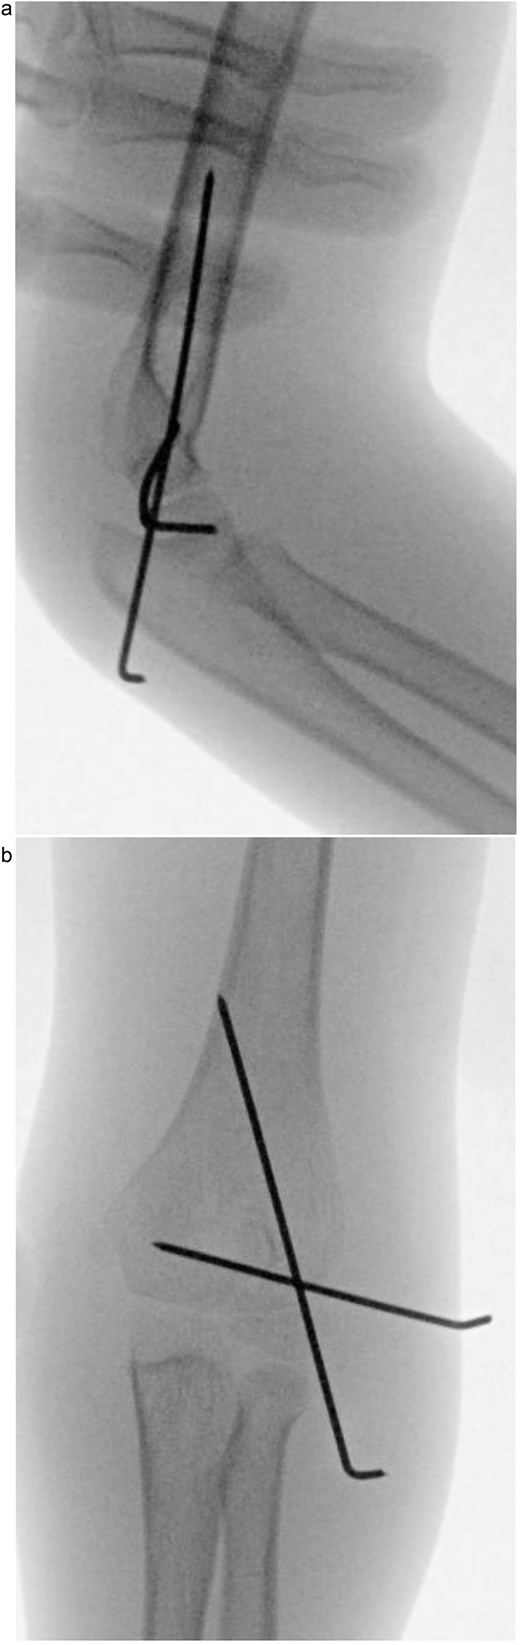

Under procedural sedation, closed reduction of the elbow dislocation was performed, restoring joint alignment and stability. However, post-reduction imaging showed persistent displacement of the lateral condyle fragment (Fig. 2a). The patient was subsequently taken to the operating room, where closed reduction of the condylar fracture was carried out under general anesthesia. As post-reduction displacement was less than 2–4 mm with intact articular cartilage, fixation was performed using two smooth Kirschner wires under fluoroscopic guidance. An arthrogram confirmed joint congruity and cartilage integrity (Fig. 3a). A long-arm posterior slab was applied with the elbow in <90° of flexion to minimize the risk of compartment syndrome (Fig. 4a).

(a) Intraoperative fluoroscopic image following closed reduction and K-wire fixation showing anatomical alignment of the lateral condyle. (b) Arthrogram confirming a congruent articular surface and stable fixation of the fracture fragment.